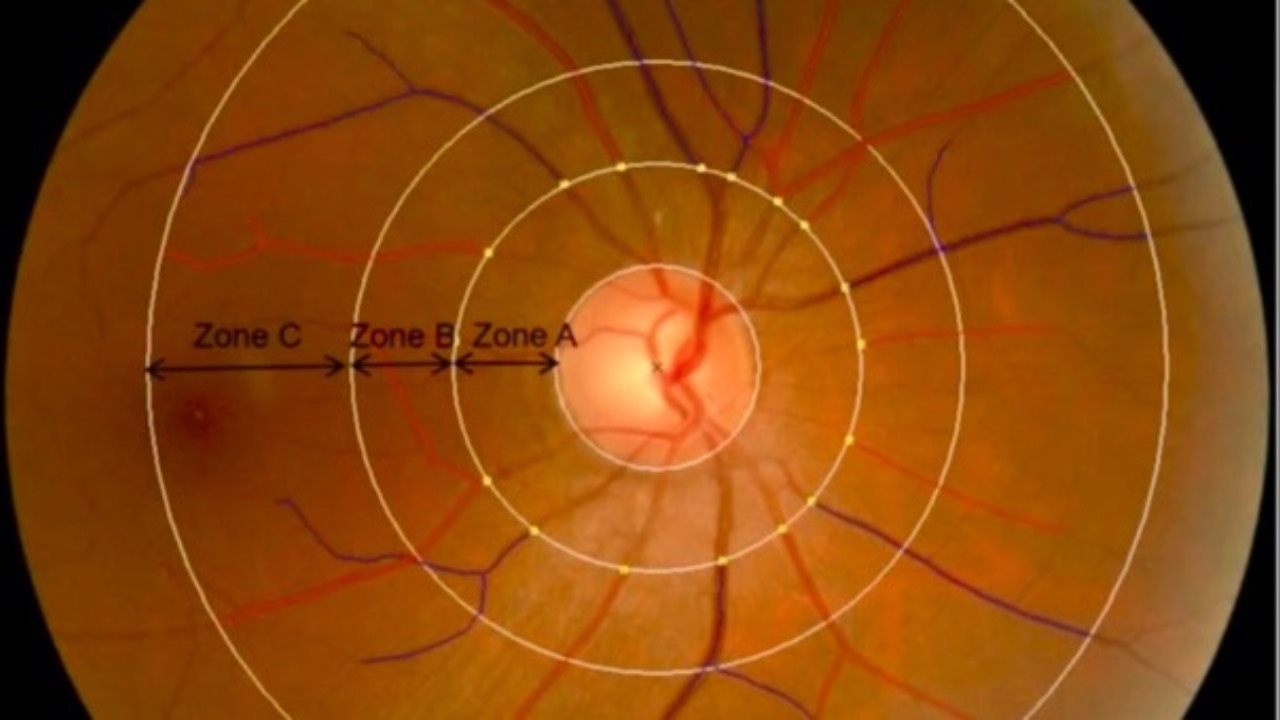

Stroke Risk & Retinal Vasculature

Do you know what to look for?...

Findings published this week uncovered a significant association between retinal vascular geometry and silent brain infarction (SBI), possibly offering us new clues in terms of stroke risk.

227 SBI patients and matched controls were studied which showed lower fra...